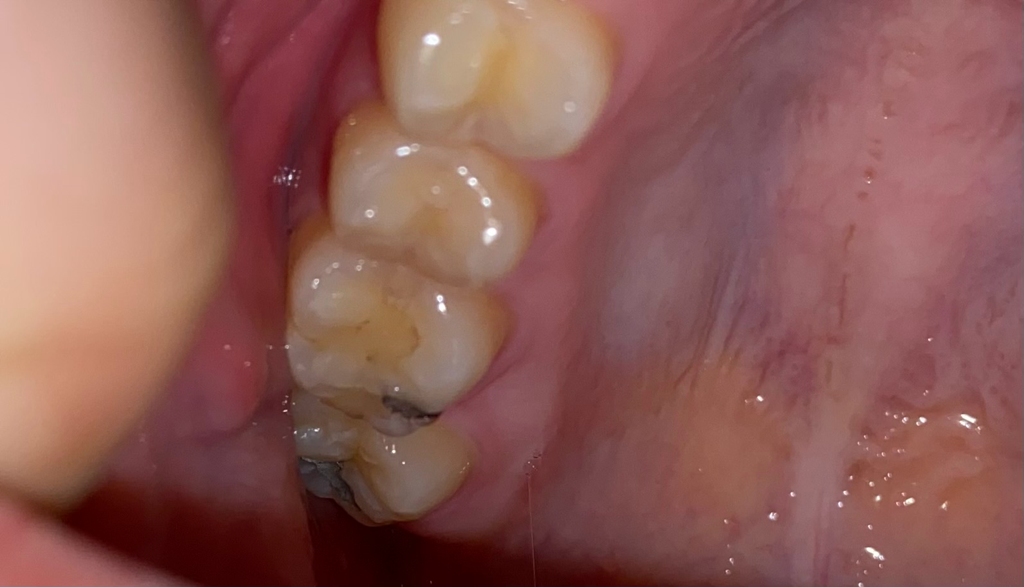

통증있는 충치 빨리 부식되나요?

오른쪽 위 어금니가 음식을 씹을 때만 아픕니다 어제 차 마실 때 뜨거운거 절 못 느꼈고 차가운 콜라 마셔도 아프지 않고 음식 씹을땨 아픕니다 구멍이 있는거 같기도 합니다

그냥 있을때도 가끔 아픕니다 특히 음식 씹을따 아픕니다

맨뒤에 있는 건 때운걸로 기억합니다 한번 봐주세요 ㅠㅠ

충치가 잇다고 치아가 부식되진 않습니다. 충치가 계속 진행되면 신경치료를 해야될 가능성이 있게되는거죠. 사진에 보이는건 예전에 치료햇던 부위가 틈이 생기면서 착색및 충치가 생긴거 같습니다. 치료를 하게되면 인레이 또는 크라운 치료를 하셔야될수도 잇을것같습니다.

1. 현재 사진상 보이는 곳은 이전에 치료를 받았던 곳으로 추측됩니다. 치아색 나는 재료로도 떼우고, 아말감이라는 은색 나는 물질로도 떼운 흔적이 보이는데 특히 아말감 수복물 주변으로 검게 된 것은 충치라기보다는 아말감 산화, 변색으로 인해 검게 변한 것으로 보시면 됩니다.

2. 현재 증상만으로는 충치가 단정지을 수 없으나 가능성은 있습니다. 그리고 씹을 때 아픈 통증은 치아 크랙도 의심해볼 수 있습니다. 평소 딱딱하거나 질긴 음식을 즐겨 드셨다면 더 가능성이 있습니다.